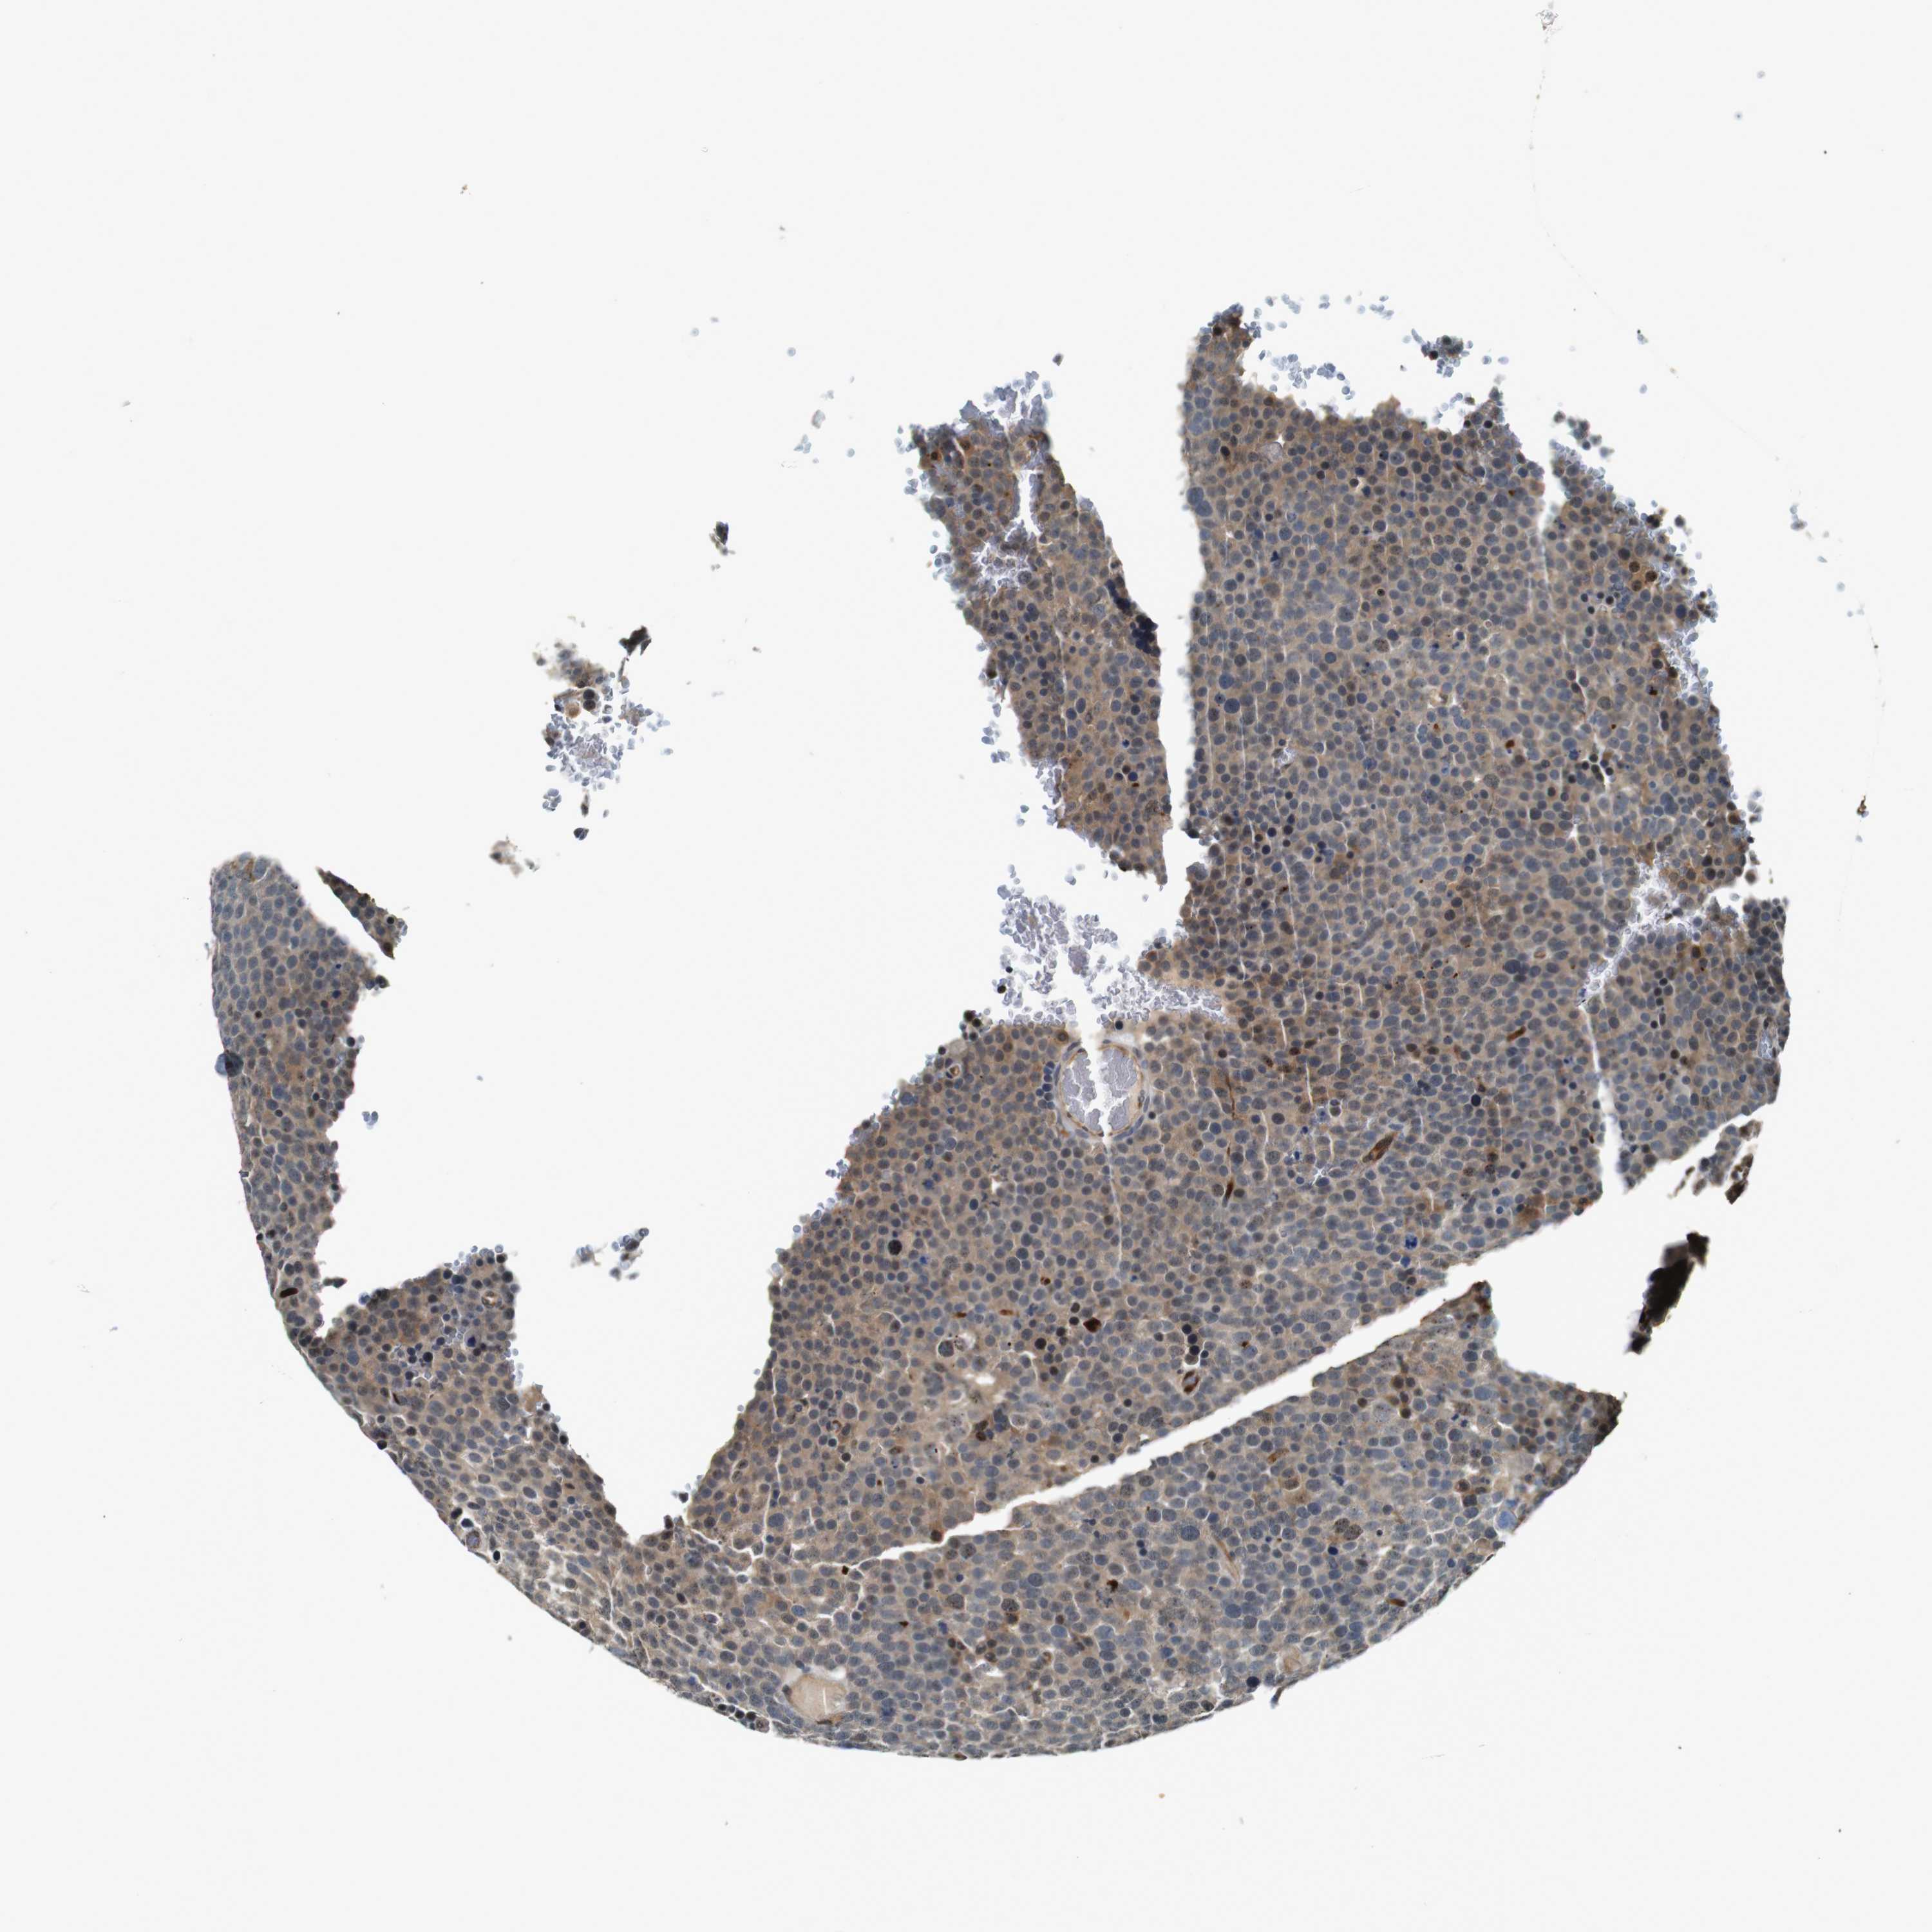

TESTIS CANCER - Protein expressioni

A mouse-over function shows sample information and annotation data. Click on an image to view it in a full screen mode. Samples can be filtered based on level of antibody staining by selecting one or several of the following categories: high, medium, low and not detected. The assay and annotation is described here.

Note that samples used for immunohistochemistry by the Human Protein Atlas do not correspond to samples in the TCGA dataset.

Antibody stainingi

Antibody staining in the annotated cell types in the current human tissue is reported as not detected, low, medium, or high, based on conventional immunohistochemistry profiling in selected tissues. This score is based on the combination of the staining intensity and fraction of stained cells.

Each image is clickable and will lead to virtual microscopy that enables deeper exploration of all samples and also displays staining intensity scores, fraction scores and subcellular localization as well as patient and tissue information for each sample.

Antibody CAB025128

Carcinoma, Embryonal, NOS

Seminoma, NOS